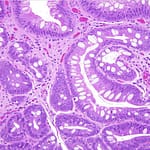

Lee sobre proteinuria en gammapatías monoclonales, Esterasa leucocitaria, carcinoma neuroendocrino de esófago, entre otros